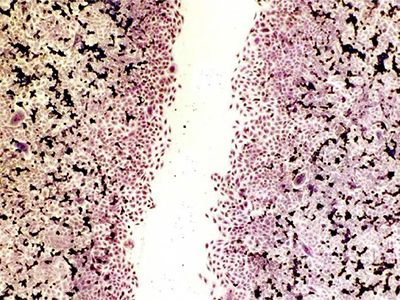

Smásjármyndir af örvuðum og óörvuðum bandvefsfrumum (fibroblastum)

Í annarri frumurannsókn (in vitro studyAn in vitro study is a scientific study conducted in an artificial environment, usually in a laboratory. In vitro studies are used to investigate the effects of substances, procedures or... More) sem framkvæmd var af Dartsch Scientific voru ræktar bandvefsfrumur notaðar til að kanna hvort tíðnisvið sem tækið sendir út gætu haft mælanleg jákvæð áhrif í frumuræktun, samkvæmt viðurkenndum og hlutlægum mæliaðferðum. Örvandi áhrif Mini-Rayone tíðnikubbsins á sáragróanda, sem áður hafa verið skráð af notendum, voru staðfest í þessari frumurannsókn. Áhrifin mældust sem næstum 20% örvun á frumustarfsemi.

Niðurstöðurnar sýna að notkun Mini-Rayone getur til dæmis stutt við og hraðað gróanda.